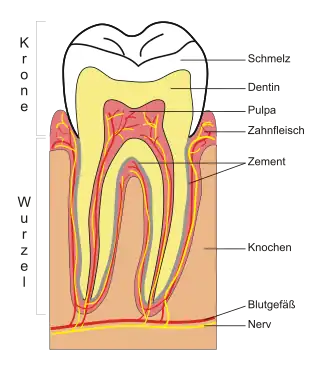

Damit menschliche Zähne eine gesunde orale Umgebung haben, müssen sich während der Embryogenese Zahnschmelz, Dentin, Wurzelzement und die Wurzelhaut (Periodontium) entwickeln. Das Milchgebiss wird ab der sechsten bis achten Woche vor der Geburt, die bleibenden Zähne in der zwanzigsten Woche angelegt.[1] Wenn die Entwicklung der Zähne nicht ungefähr zu dieser Zeit beginnt, findet sie gar nicht statt. Nach allgemeiner Ansicht ist ein Faktor im Gewebe des ersten Kiemenbogens notwendig, um den Prozess zu initiieren.[1]

Zahnschmelz

Die Bildung von Zahnschmelz, auch Amelogenese genannt, ereignet sich während des Kronenstadiums. Die Formation von Dentin und Zahnschmelz ist durch eine reziproke Induktion gekennzeichnet; Dentin entsteht immer vor dem Zahnschmelz. Letzterer bildet sich in zwei Phasen. In der sekretorischen Phase bilden Proteine und eine organische Matrix einen teilweise mineralisierten Zahnschmelz, in der Reifephase wird die Mineralisierung abgeschlossen. (Cate 1998:197)[1]

Die Mineralisierung in der ersten Phase erfolgt durch das Enzym Alkalische Phosphatase. (Ross 2003:445)[3] Das üblicherweise im dritten oder vierten Monat der Schwangerschaft auftretende mineralisierte Gewebe stellt das erste Auftreten von Zahnschmelz im Körper dar, der sich dann nach außen ausbreitet.

In der Reifephase transportieren die Ameloblasten einige bei der Produktion von Zahnschmelz benutzten Substanzen nach außen. Dabei handelt es sich hauptsächlich um Proteine, die zur vollständigen Mineralisation am Ende dieses Stadiums verwendet werden. Die wichtigsten Proteine sind Amelogenin, Ameloblastin, Enamelin und Tuftelin. (Ross 2003:447)[3]

Dentin

Die als Dentinogenese bezeichnete Bildung von Dentin ist das erste erkennbare Merkmal im Kronenstadium. Die verschiedenen Stufen führen zu unterschiedlichen Arten von Dentin: Manteldentin (Korff-Dentin) sowie primäres, sekundäres und tertiäres Dentin.

Die dentinbildenden Odontoblasten differenzieren sich von den Zellen der Zahnpapille. Sie beginnen, eine organische Matrix rund um die zukünftige Spitze des Zahns nahe dem inneren Epithel abzusondern. Diese Matrix enthält Collagen-Fasern mit einem großen Durchmesser von 0,1–0,2 μm. (Cate 1998:136)[1] Die Odontoblasten bewegen sich zum Zentrum des Zahns und bilden einen Ableger, den man als Odontoblasten-Prozess bezeichnet. (Cate 1998:95)[1] Dieser führt zur Sekretierung von Hydroxyapatit-Kristallen und zur Mineralisation der Matrix. Die etwa 150 μm dicke Schicht ist das Manteldentin. (Cate 1998:138)[1]

Während das Manteldentin aus einer bereits existierenden Grundsubstanz der Zahnpapille entsteht, entwickelt sich das primäre Dentin auf andere Weise. Die Odontoblasten werden so groß, dass keine extrazellulären Ressourcen zu einer organischen Matrix beitragen können. Die größeren Odontoblasten sondern das Kollagen in kleineren Mengen ab, wodurch klarer strukturierte, heterogene Kerne entstehen. Darüber hinaus werden weitere Substanzen wie Lipide, Phosphoproteine und Phospholipide abgesondert. (Cate 1998:139)[1]

Das sekundäre Dentin wird – wesentlich langsamer – nach Abschluss der Wurzelformation gebildet. Die Entwicklung verläuft in der Nähe der Krone schneller ab als an anderen Stellen des Zahns. (Summit 2001:13)[6] Sie dauert während des ganzen Lebens an und ist verantwortlich für die kleinere Pulpa bei älteren Menschen. (Cate 1998:128)[1] Das tertiäre Dentin (auch als reparierendes Dentin bekannt) entsteht in Reaktion auf Reize wie Abkauung oder Zahnkaries. (Summit 2001:183)[6]

Wurzelzement

Die als Zementogenese bezeichnete Bildung des Wurzelzements ereignet sich zu einem späten Zeitpunkt in der Entwicklung der Zähne. Zementoblasten sind die dafür verantwortlichen Zellen. Es gibt zwei Arten von Wurzelzement: zellulär und azellulär.[7]

Die azelluläre Variante bildet sich zuerst. Die Zementoblasten differenzieren sich von Follikel-Zellen, die die Oberfläche der Zahnwurzel erst erreichen können, wenn die Hertwig’sche Epithelscheide („Hertwig’s Epithelial Root Sheath“ – HERS) zu verfallen beginnt. Die Zementoblasten sondern feine Kollagenfibrillen rechtwinklig zur Wurzeloberfläche ab, bevor sie sich vom Zahn weg bewegen. Unterwegs wird mehr Kollagen abgelagert, um die Faserbündel zu verlängern und zu verdicken. Weitere Proteine wie Knochen-Sialoprotein und Osteocalcin werden ebenfalls abgesondert. (Cate 1998:236)[1] Der azelluläre Wurzelzement enthält eine Sekret-Matrix aus Proteinen und Fasern. Wenn die Mineralisation beginnt, entfernen sich die Zementoblasten vom Wurzelzement und die zurückbleibenden Fasern an der Oberfläche verbinden sich mit den periodontalen Bändern.

Der zelluläre Wurzelzement entsteht, wenn die Zahnbildung fast abgeschlossen ist und der Zahn (in Kontakt) mit einem gegenüberliegenden Zahn verschließt. (Cate 1998:241)[1] Er bildet sich rund um die Faserbündel der periodontalen Bänder. Die Zementoblasten werden in dem von ihnen produzierten Wurzelzement eingeschlossen.

Die Herkunft der Zementoblasten ist bei beiden Arten von Wurzelzement unterschiedlich. Die geläufigste Hypothese besagt, dass die Zellen für den zellulären Wurzelzement vom benachbarten Knochen herkommen, während die Zellen für die azelluläre Sorte aus dem Zahnfollikel stammen (Cate 1998:241 und 243).[1] Zellulärer Wurzelzement findet sich jedoch nicht in Zähnen mit einer Wurzel (Cate 1998:241).[1] Bei Prämolaren und Backenzähnen findet man ihn nur in der Nähe der Wurzelspitze und zwischen den einzelnen Wurzeln.

Bildung des Periodontiums